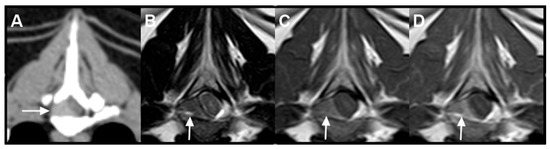

Multicentric Round Cell Neoplasia with Plasmacytic Differentiation in a Cat with Systemic Progression: Multimodal Imaging and Treatment Response

Plasma cell neoplasia is uncommon in cats, and multicentric nodal-predominant involvement has not been well characterized. This report describes a multicentric round cell neoplasia with plasmacytic differentiation in a 14-year-old Domestic Shorthair cat, emphasizing multimodal imaging features and treatment response. Contrast-enhanced computed tomography [...] Read more.

Plasma cell neoplasia is uncommon in cats, and multicentric nodal-predominant involvement has not been well characterized. This report describes a multicentric round cell neoplasia with plasmacytic differentiation in a 14-year-old Domestic Shorthair cat, emphasizing multimodal imaging features and treatment response. Contrast-enhanced computed tomography and magnetic resonance imaging were performed for staging and longitudinal assessment. Cytomorphology supported plasmacytic differentiation, and flow cytometry did not demonstrate an immunophenotype consistent with conventional B- or T-cell lymphoma. Because histopathology, immunohistochemistry, bone marrow evaluation, and assessment for monoclonal gammopathy were not performed, definitive classification was not possible; however, cytomorphology supported plasmacytic differentiation, with plasma cell neoplasia remaining an important diagnostic consideration. A hypofractionated radiotherapy protocol (36 Gy in six fractions) combined with systemic chemotherapy was administered. Serial imaging demonstrated complete radiologic resolution of the irradiated mass, whereas non-irradiated presumed nodal lesions progressed and an extradural spinal lesion subsequently developed. These findings highlight the capacity of round cell neoplasia with plasmacytic differentiation to mimic lymphoma on imaging and illustrate the dissociation between effective local control and ongoing systemic progression. Full article

(This article belongs to the Special Issue Abdominal Imaging in Small Animals: New Insights)

Show Figures

Figure 1